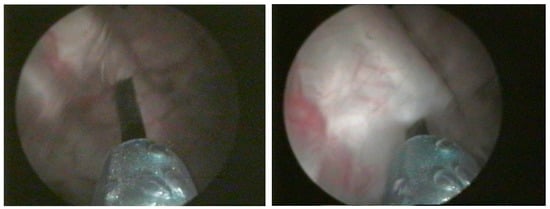

2. Materials and Methods